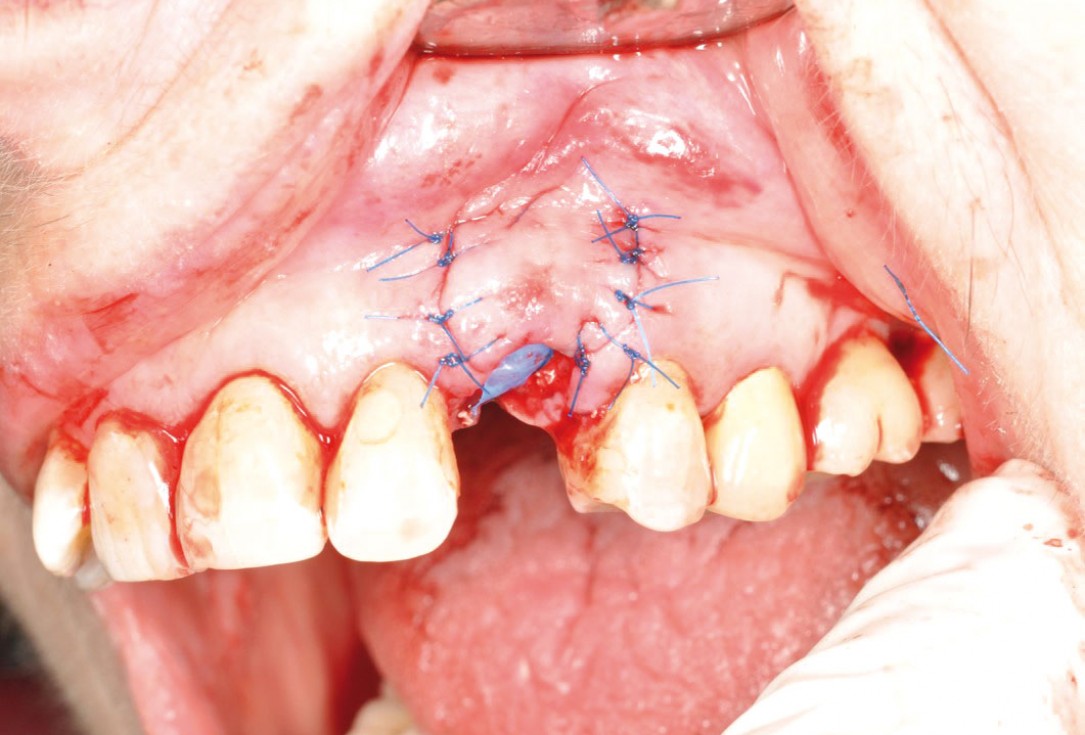

GBR with cerabone® and Jason® membrane in the front tooth region - Dr. H. Maghaireh

Initial clinical situation with gum recession and labial bone loss eight weeks following tooth extraction